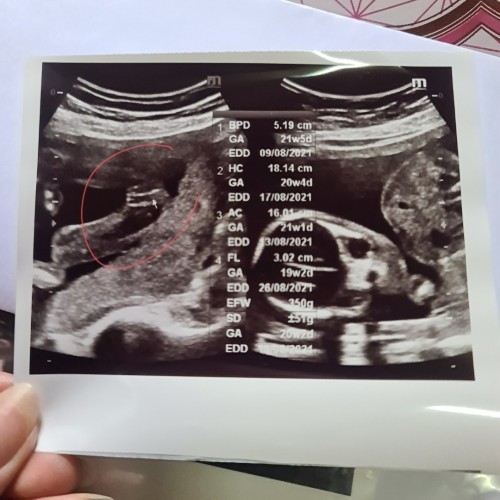

ลูกสาวค่ะ 21w